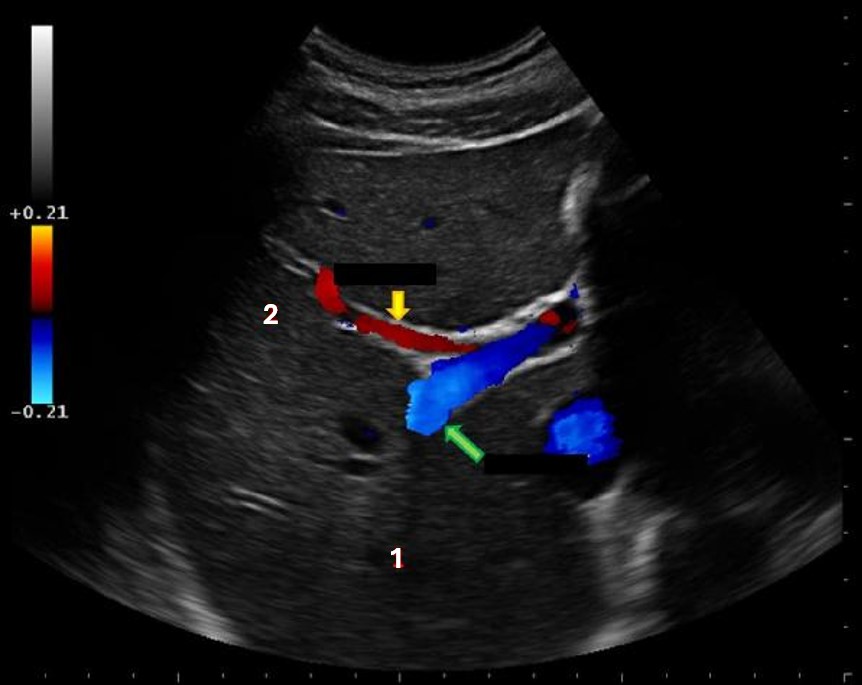

What structure is indicated by the yellow arrow?

main lobar fissure |

The yellow arrow on the images represents which of the following structures?

|

What liver vessel is indicated by the green arrow?

posterior right portal vein |

What structure is indicated by the blue arrow?

right portal vein |

What structure is indicated by the green arrow?

Main portal vein |

What structure is indicated by the red arrow?

|